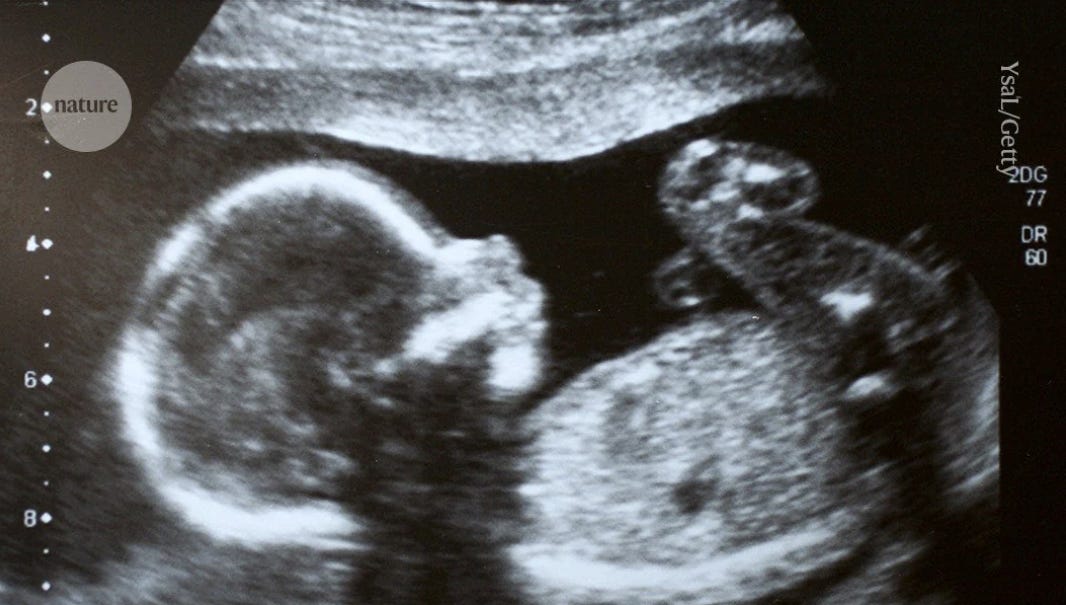

Rare genetic disorder treated in womb for the first time…

A two-and-a-half-year-old girl shows no signs of a rare genetic disorder, after becoming the first person to be treated with a gene-targeting drug while in the womb for spinal muscular atrophy, a motor neuron disease. The “baby has been effectively treated, with no manifestations of the condition.”